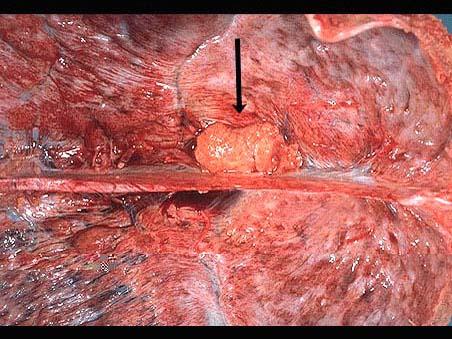

问题 老年女尸,生前行CT检查见矢状窦旁有一低密度影,周边有轻度水肿带。尸检标本大体如图所示,镜检如图所示,请作出诊断 ( )

选项 A.矢状窦旁髓母细胞瘤 B.矢状窦旁星形细胞瘤 C.矢状窦旁室管膜瘤 D.矢状窦旁脑膜瘤 E.矢状窦旁脑脓肿

答案 D